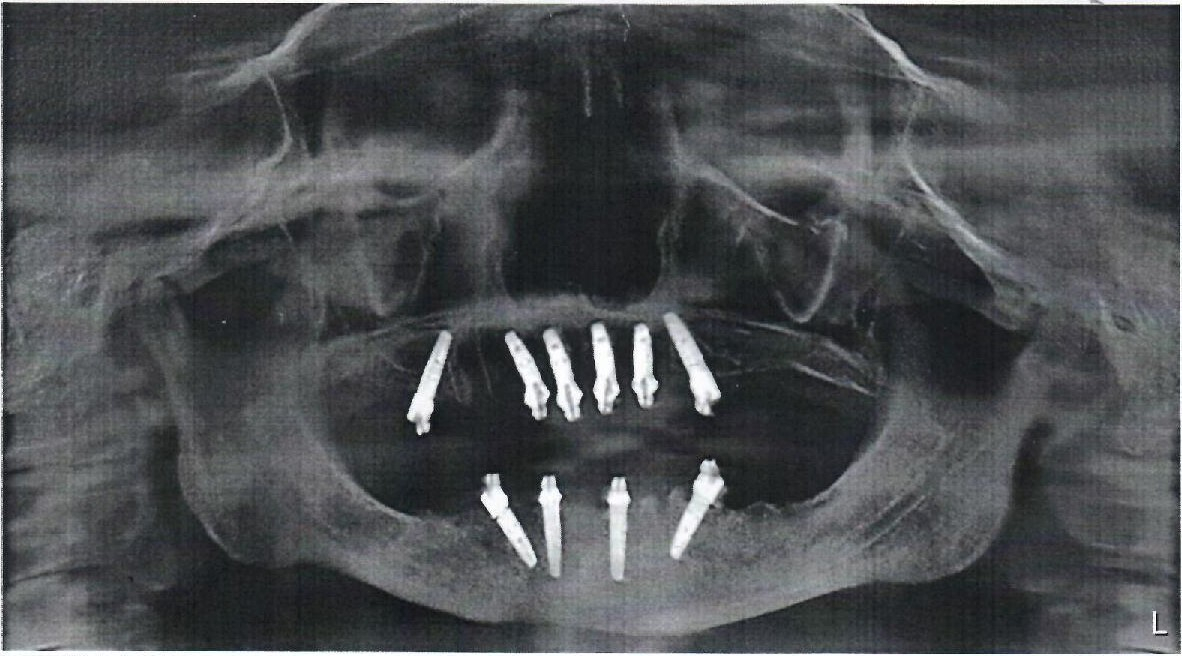

— Наши врачи постоянно сталкиваются со сложными ситуациями, которые требуют тщательного подхода к решению проблемы полости рта. На фото вы можете видеть примеры наших работ.